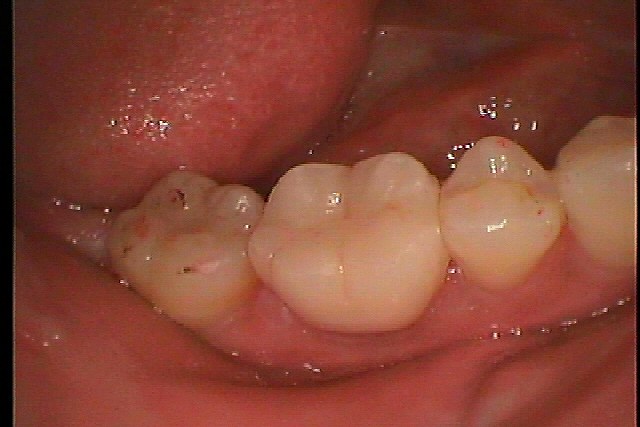

右下6番 きれいな白いセラミックに変えたいとのこと|お知らせ |広島市安佐南区の歯科医院 右下6番 きれいな白いセラミックに変えたいとのこと トップ お知らせ・ブログ お知らせ 右下6番 きれいな白いセラミックに変えたいとのこと 右下6番 きれいな白いセラミックに変えたいとのこと この銀歯が昔から気になるとのこと レントゲンにて 根の病気はなさそうです 土台を外し中の状態を見ていきます 割れていないかの確認も取ります ファイバーコアにて築造を行っています 支台築造後セラミッククラウンの型取りを行っていきます オールセラミッククラウンになります 綺麗に仕上がりました Web診療予約 初めての方へ 選ばれ続ける理由 院内設備について 歯が痛いしみる一般歯科 歯がぐらぐらする歯周病 健康な歯を保ちたい予防歯科 子供の虫歯予防をしたい小児歯科 銀歯をセラミックに審美歯科 白い歯を目指しませんか?ホワイトニング 矯正専門医がいるので安心矯正歯科 抜けた歯を補いたいインプラント・入れ歯 医院案内 スタッフ紹介 メリィハウス歯科クリニックオフィシャルホームページ ラベンダー歯科クリニックオフィシャルホームページ お知らせ・ブログ ホーム 診療科目 一般歯科 歯周病治療 予防治療 小児歯科 審美治療 ホワイトニング 矯正歯科 入れ歯・インプラント マウスピース矯正 初めての方へ 院長・スタッフ 設備紹介 医院案内・アクセス メニューを閉じる